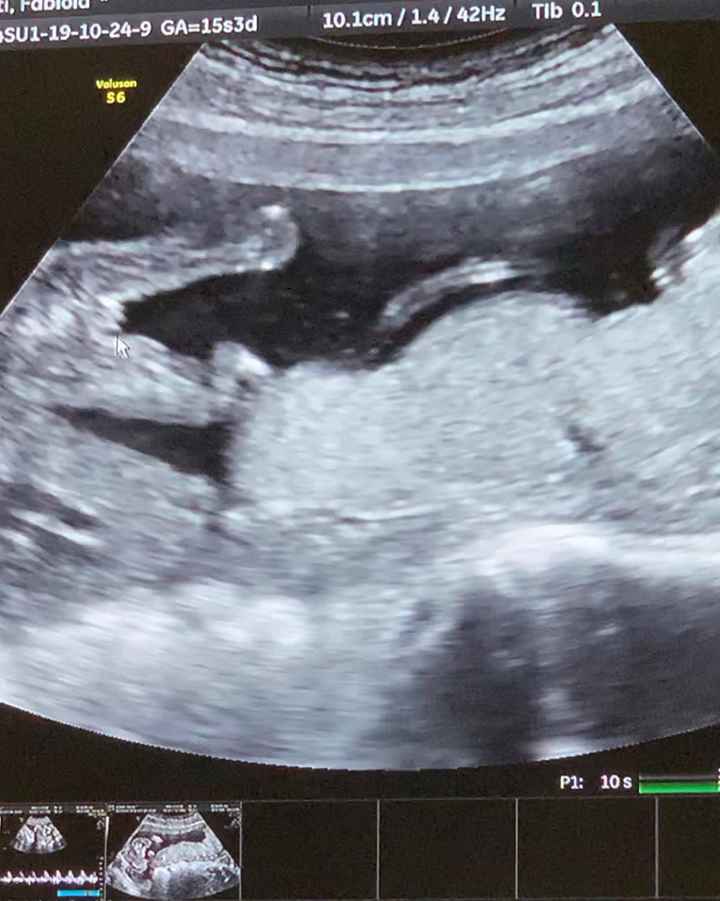

'Verona', Verona ยท Da Agosto 2018

15 Giugno 2019